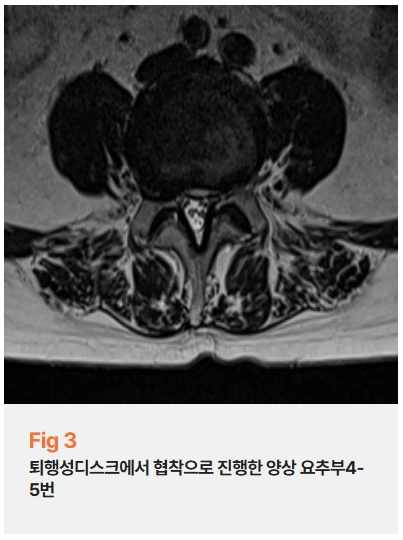

퇴행성 디스크, 요추 4-5번 척추관협착증으로 인한 신경눌림증,

그리고 양측 고관절 충돌증후군까지 세 가지가 겹쳐 있었거든요.

%EA%B7%B8%EB%A6%BC3.png?type=w966

고관절 가동 범위를 측정해보니 외회전이 20도밖에 되지 않았어요.

이건 오십견 환자분들의 어깨 각도와 비슷한 수준이에요.

그만큼 고관절이 굳어있었던 거죠.